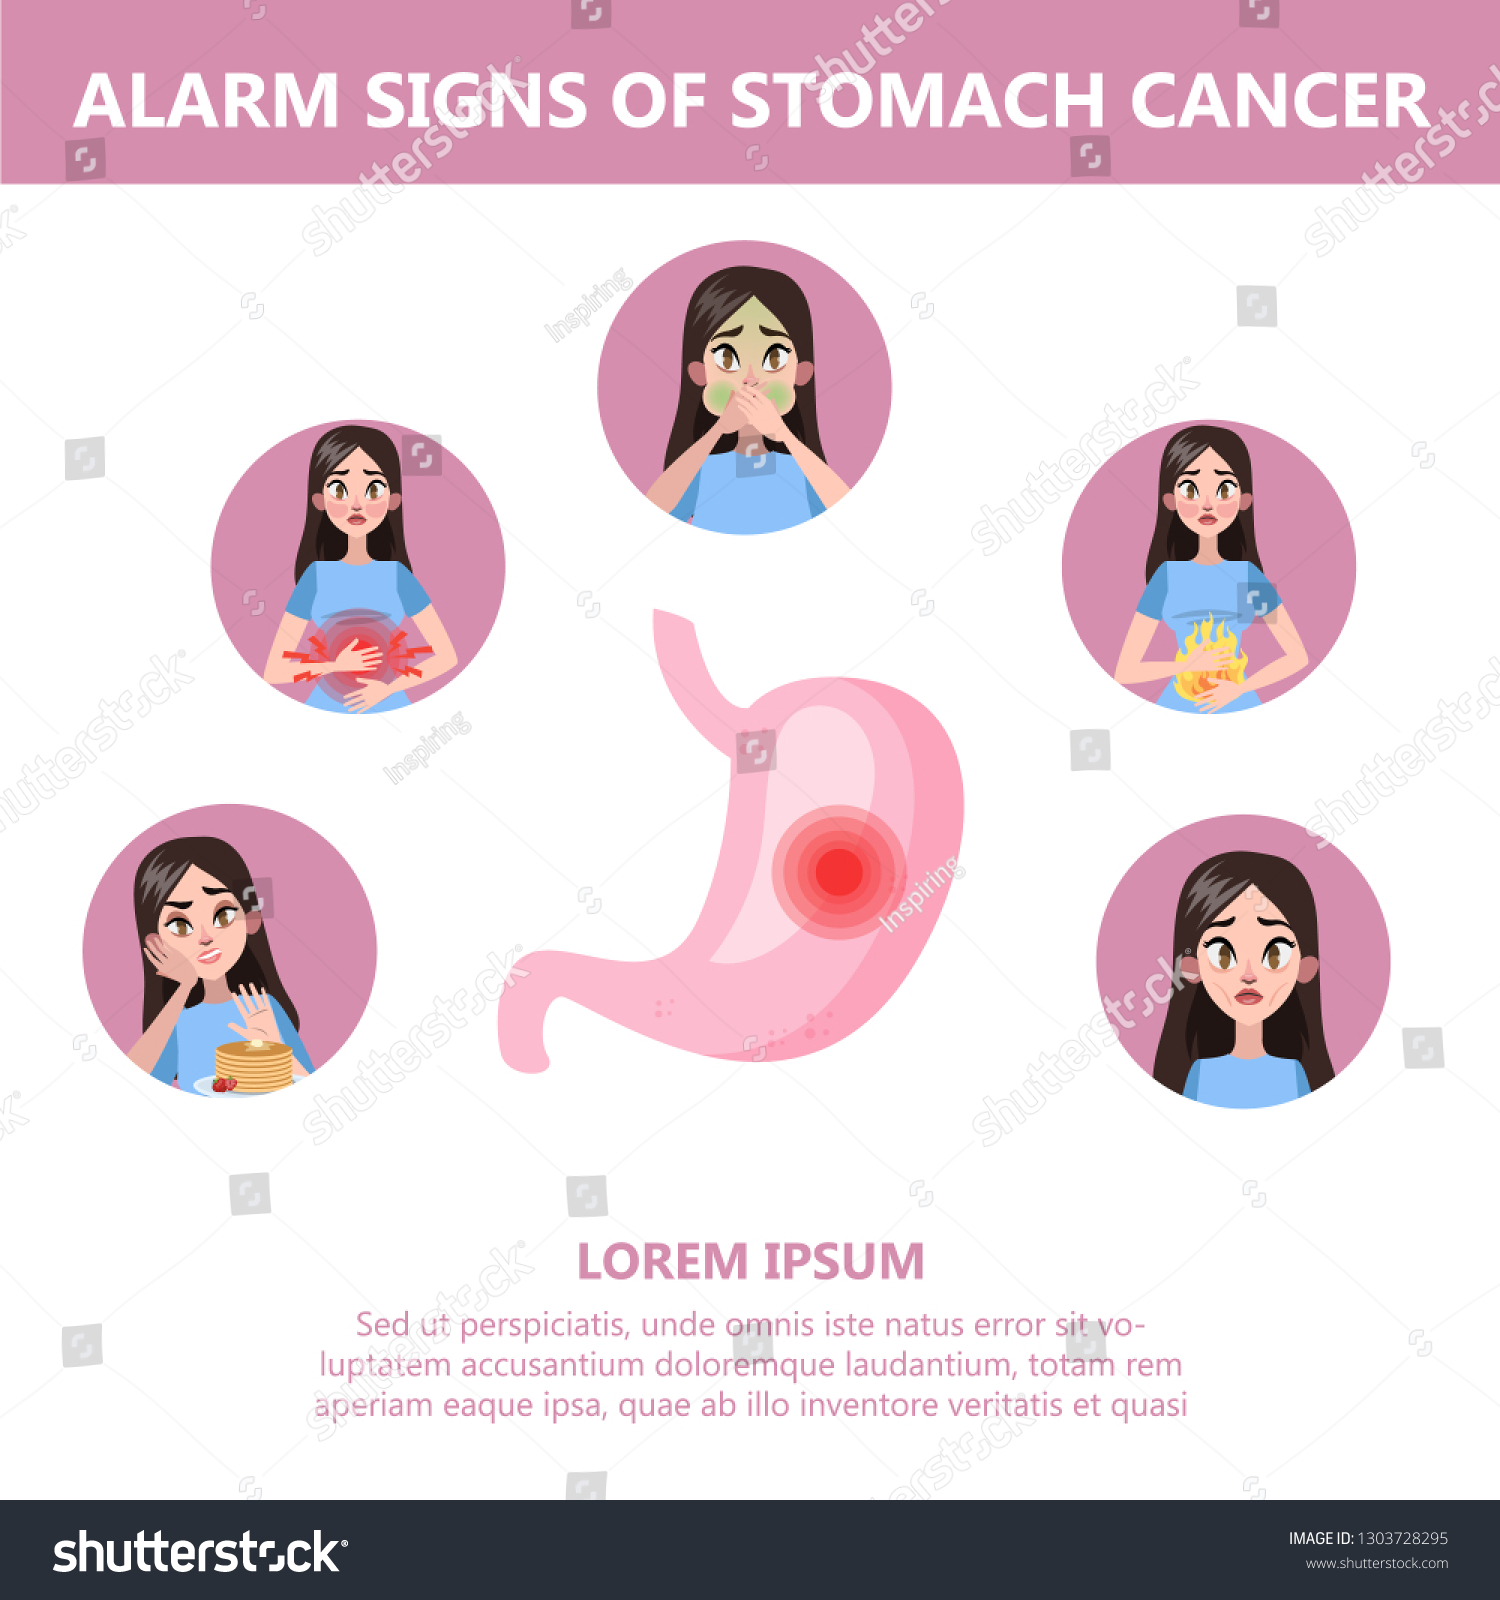

Warning signs of stomach cancer

What Symptoms Do You Have If You Have Stomach Cancer : Quickly See If …

Warning Signs And Risk Factors for Stomach Cancer! – By Dr. Nikhil …

6 Warning Signs of Stomach Cancer – Health | Katalay.net

What Are The Symptoms Of A Tumor In The Stomach / Gastric Cancer Cancer …